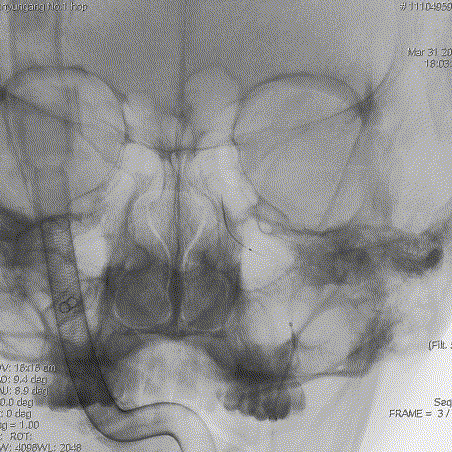

DSA提示双侧颈内动脉C5以远闭塞(右颈)

DSA提示双侧颈内动脉C5以远闭塞(左颈)

DSA提示后循环代偿双侧前循环,左侧大脑后动脉远端闭塞(右椎)

DSA提示后循环代偿双侧前循环,左侧大脑后动脉远端闭塞(左椎)

3D-DSA提示右侧椎动脉V4夹层动脉瘤

DSA提示右侧椎动脉V4夹层动脉瘤